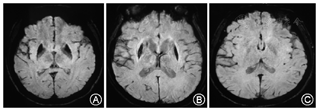

通过独立样本t检验,脑型WD患者右侧尾状核、左侧壳核SWI相位值较肝型WD患者低(P值分别为:0.020,0.23,图3)。

SWI是检测脑部金属沉积的有效方法,铁、锰、铜和钙可被SWI检测出来。SWI可定量测量物质的磁敏感效应引起的相位值的改变,从而间接估计该物质的含量,可作为测定物质浓度的非侵入性方法[8,9,10,11,12]。WD患者脑病核团相位值改变可能是铜和铁共同作用的结果。我们通过SWI研究发现,肝型WD患者黑质、尾状核、壳核、丘脑、小脑等部位的SWI相位值较正常降低,提示这些核团有金属的沉积。有研究认为肝型和脑型WD脑铜含量无差别[13]。在我们对脑型和肝型SWI相位值的比较中可见,脑型WD患者在壳核、尾状核等部位的相位值低于肝型,提示肝型WD患者脑部某些核团金属含量低于脑型。但是肝脑型WD患者核团SWI相位值的差异并不显著,肝型WD患者脑部金属沉积量与脑型相比并无太大差异。导致肝型WD患者未出现神经症状的原因,可能并不是肝型患者脑部金属沉积少,而是脑部结构性损伤不显著。但为何肝型患者脑部金属沉积明显,而结构性损伤较轻,原因尚不明确。可能除了金属沉积之外,还有其他原因,导致WD患者脑部的结构性损伤,这尚需进一步研究证实。另外,肝型WD患者脑部金属沉积与肝功等级无关,肝功能情况不会影响金属在脑部的沉积。